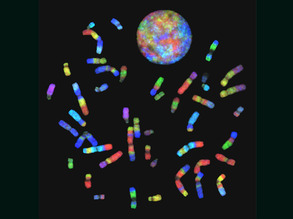

Code-A-Chrome

16